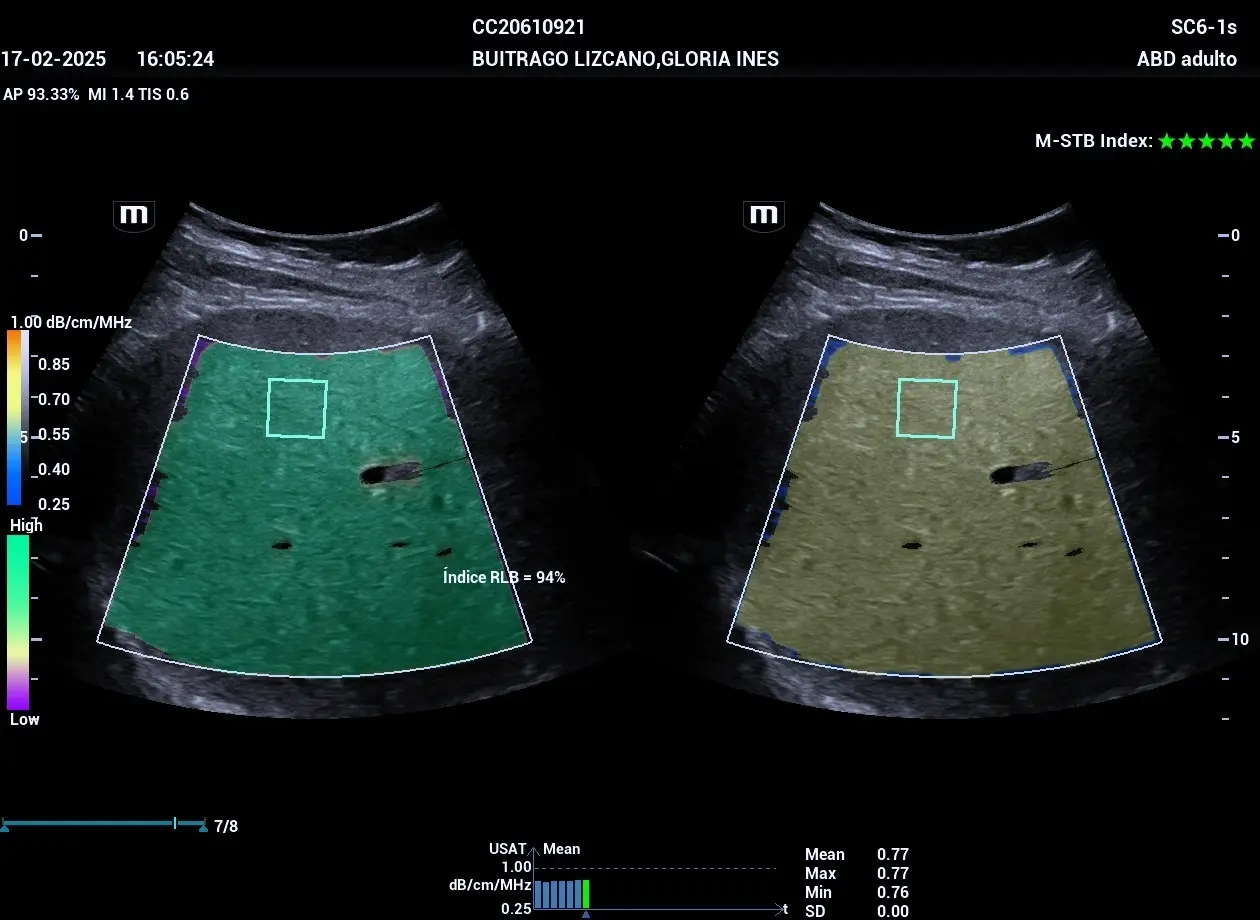

Realización de una ecografía abdominal